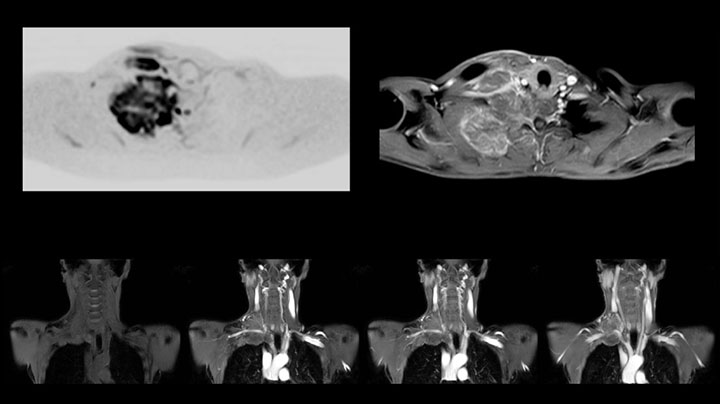

This patient is a 43-year-old female with a left supraclavicular nerve sheath tumor. The lesion is well visualized on the STIR VISTA images and on the MR neurography using DWIBS. The exam was performed on Prodiva 1.5T.

Acq voxel size 1.2 x 1.3 x 2.4 mm, Recon voxel size 0.7 x 0.7 x 1.2 mm, dS SENSE factor 2, scan time 5:46 min.